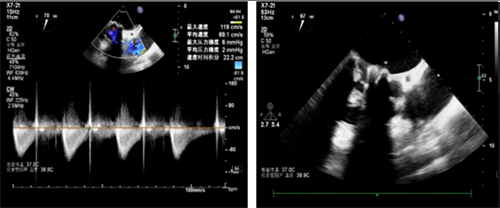

8、学科辐射力显著增强,新增新技术59项,经导管二尖瓣钳夹术、经支气管镜蒸汽肺减容术、经心尖心脏瓣膜介入手术、经颈静脉肝内门体分流术5项技术达到国内领先水平;设置28项战略术种,激励高精尖外科手术的开展。